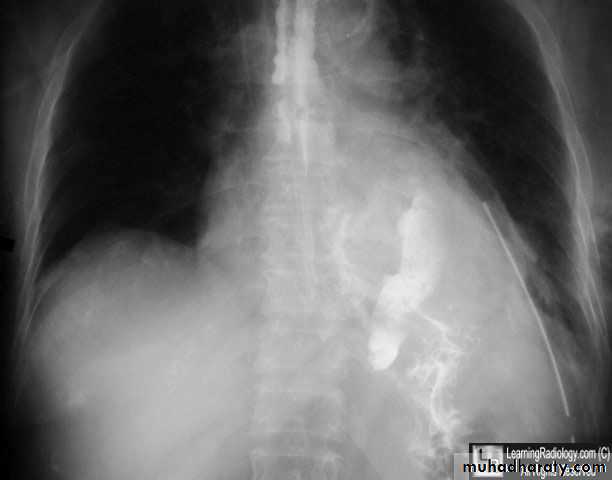

Corrosive injury

In attempted suicide or accidental ingestion these injuries may occur by eg: NaOH or sulphuric acid.These agents either acid or alkali.

Alkali are tasteless and colorless so its ingestion is more common.

Alkali cause liquefaction and fibrous scarring.

While acids cause coagulative necrosis and eschar formation.

Acids cause intense pylorospasm with pooling in the antrum so causing more gastric damage.

Treatment:The key is early endoscopy, to determine the extent of damage and subsequent treatment.

If mild so early feeding

If sever with ulceration so feeding jejunostomy.

If there is perforation do esophagectomy.

When stricture develop later so treatment is either:Dilatation if small stricture or esophagectomy if large one.

Figure 7: stricture following corrosive injury.